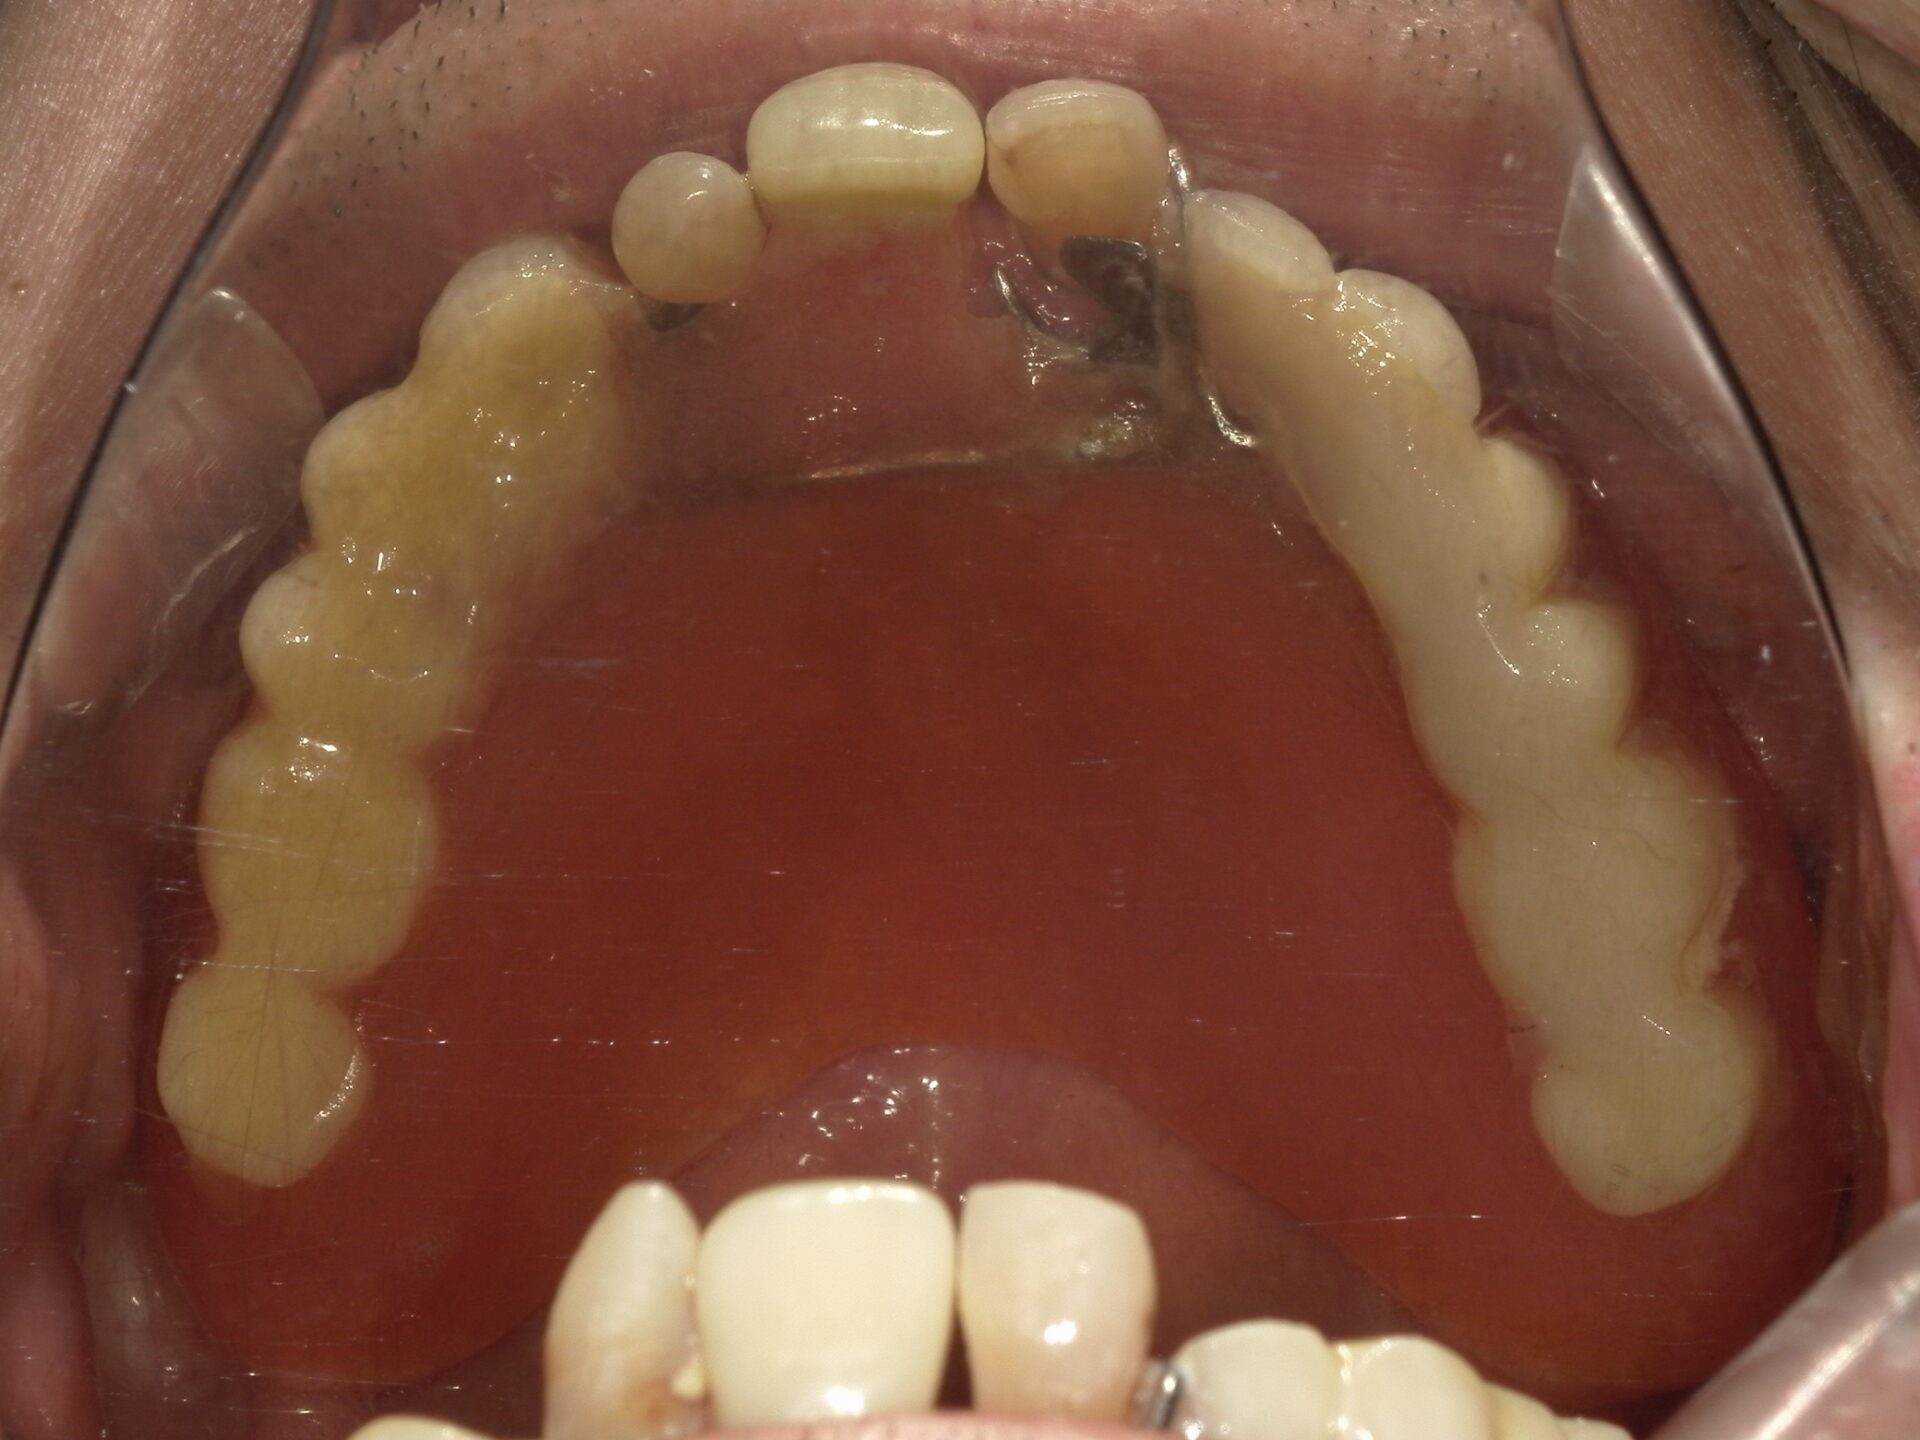

before

患者さんの年齢 30代 女性 症状 見た目がコンプレックス 治療内容 マウスピース矯正治療(抜歯あり) 費用 90万(税抜) 治療期間・回数 治療期間2年、通院回数10回 デメリット・リスク 期間がかかることがある 患者さまの声 なんでも噛める。本当に治療して良かった。 - 矯正治療